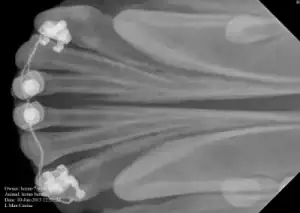

This radiograph shows the three incisor at the top of the image have been displaced from their sockets

The same teeth have been replaced in the socket. Buttons and wire have been used to stabilise these teeth allowing the torn ligament of the teeth to repair